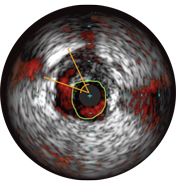

Vessel diameters may be determined at proximal and distal reference sites by obtaining lumen diameters, mid-wall diameters (halfway between lumen and vessel), or vessel diameters, in order of increasing aggressiveness.

If maximum and minimum diameters are used, measurements should bisect the geometric center of the vessel rather than the center of the IVUS catheter.

Malapposition is identified by blood behind the stent struts. ChromaFlo imaging colors blood flow red for easy recognition of malapposition and other lumen features.